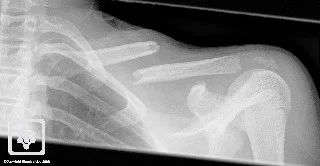

Clavicle Fracture: Management

- Non or minimal displaced: Typically conservative: heals well

- Figure-of-eight brace (bandage)

- Or Shoulder sling holding the elbow to overcome gravity